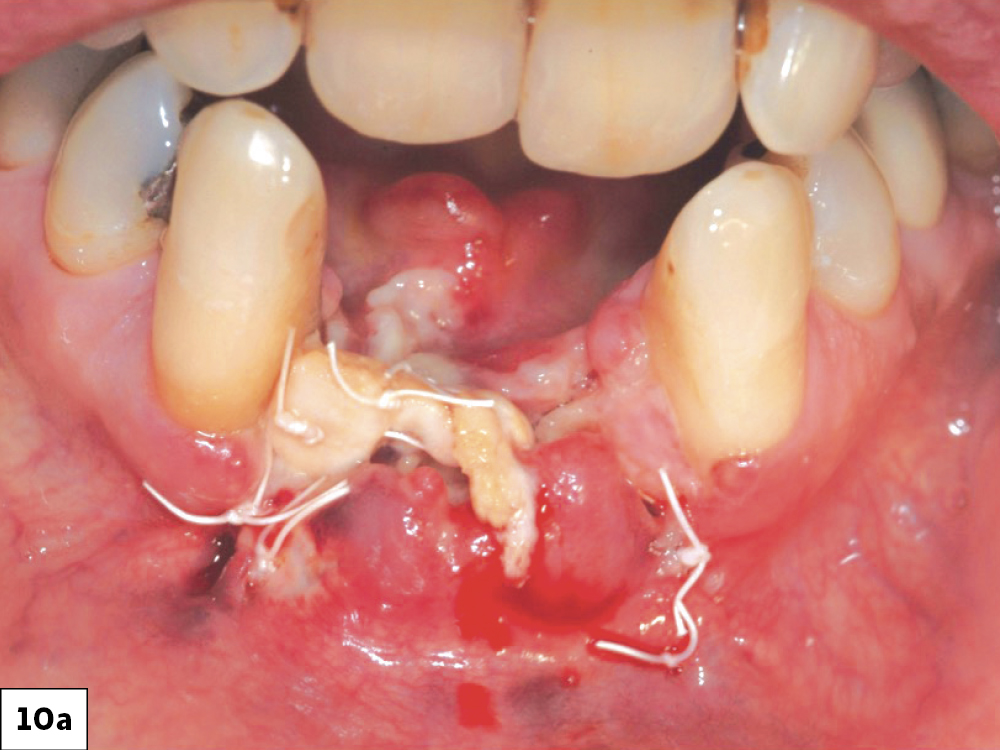

Resuturing wound dehiscences is a challenging procedure, which often results in delayed and unpredictable healing (Fig. 10). Attempting to resuture a fresh wound, particularly when the epithelium is thin and friable, often leads to tearing of the incision line, potentially causing a larger dehiscence or infection. Therefore, resuturing should be approached with care. Greenstein et. al., suggest that resuturing is more viable when the dehiscence is small and occurs within 24 to 48 hours.2 As the wound enlarges (2 to 3 cm) or the time elapsed exceeds 2 to 3 days, the feasibility of excising and resuturing is decreased and commonly results in increased morbidity and should not be attempted.8

Resuturing ILO: (a) Oneweek post-op following bone graft, (b) Twoweek post-op after unsuccessful re-suturing of the surgical wound.

Figures 10a, 10b: Resuturing ILO: (a) One-week post-op following bone graft, (b) Two-week post-op after unsuccessful re-suturing of the surgical wound.